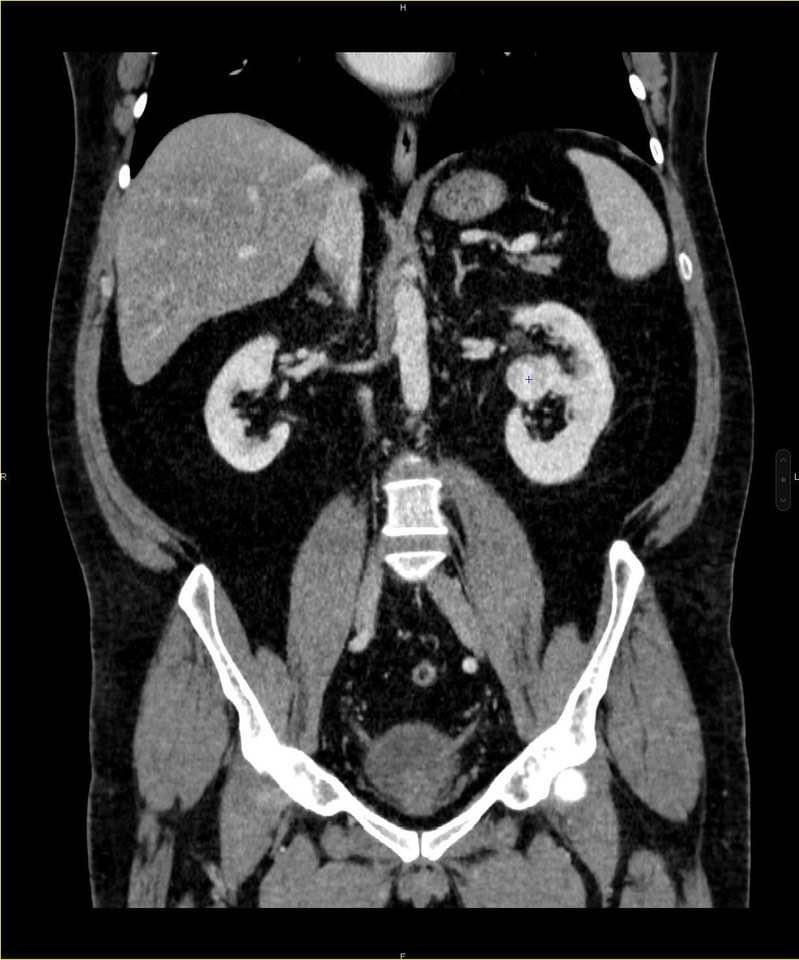

„Am cultura preventiei si cred ca este cea mai corecta abordare, cel putin in cazul meu. Am o serie de afectiuni pe care le controlez si le gestionez, dar si fara aceste probleme la fel as face. Asa am depistat si cancerul renal, facand un test PSA pentru prostata. Rezultatul a fost unul care ridica semne de intrebare asa ca am urmat procedura: am facut RMN, apoi un CT renal, pentru ca acolo parea sa fie ceva si-au gasit acea tumora renala. S-a stabilit ca este un cancer renal cu celule renale in stadiul I”, povesteste George, cu dezinvoltura omului care a trecut prin suferinta si a fost eliberat.

„Cazul despre care vorbim a fost unul dificil. Chiar foarte dificil ca urmare a pozitiei in care s-a dezvoltat formatiunea maligna, respectiv in centrul rinichiului, cu o varianta vasculara cu trifurcarea arterei care cuprinde nodul tumoral, ca si cum ar fi fost intr-o colivie. Dar scopul meu a fost de la bun inceput acela de a salva integritatea renala, iar pentru pentru a o realiza efectuat o tumorectomie (scoaterea exclusiv a tumorii)”, explica medicul chirurg.

Masele renale sunt clasificate in functie de pozitia, dimensiunea tumorii si riscul asociat, cele mai utilizate scoruri fiind Padua Score si R.E.N.A.L. Score. Acestea sunt proportionale cu riscul de a se produce complicatii in timpul interventiei, deci dificultatea procedurii chirurgicale. Mai mult decat atat, verificarea acestor complicatii in timpul operatiei de extirpare a masei tumorale poate determina chiar si necesitatea schimbarii strategiei chirurgicale, adica nefrectomia.

„A existat un scor al interventiei. Am luat in calcul ca pot sa apara evenimente care sa impuna sacrificarea rinichiului. Aceasta interventie a avut scorul de risc 14, valoarea maxima fiind 16. Un scor inalt e asociat cu complicatii mai multe, fie pentru ca pozitia tumorii este greu abordabila, fie pentru ca masa este mare, cu un diametru de peste 4 cm, fie pentru ca vascularizarea este de asa natura ca poate produce leziuni vasculare in timpul disectiei. O masa tumorala mare poate produce daune in zonele imediat limitrofe. Toate situatiile posibile sunt cuantificate in acest scor”, explica dr. urolog, care a adaugat: „Tehnica chirurgicala utilizata in aceasta interventie, excizie fara clamparea arterei renale, a fost una de performanta, pentru ca scopul a fost acela ca pacientul sa-si pastreze ambii rinichi functionali, iar in aceste conditii interventia capata o semnificatie majora, mai ales in lupta intre maxima chirurgie suportata si cea minim eficace!”